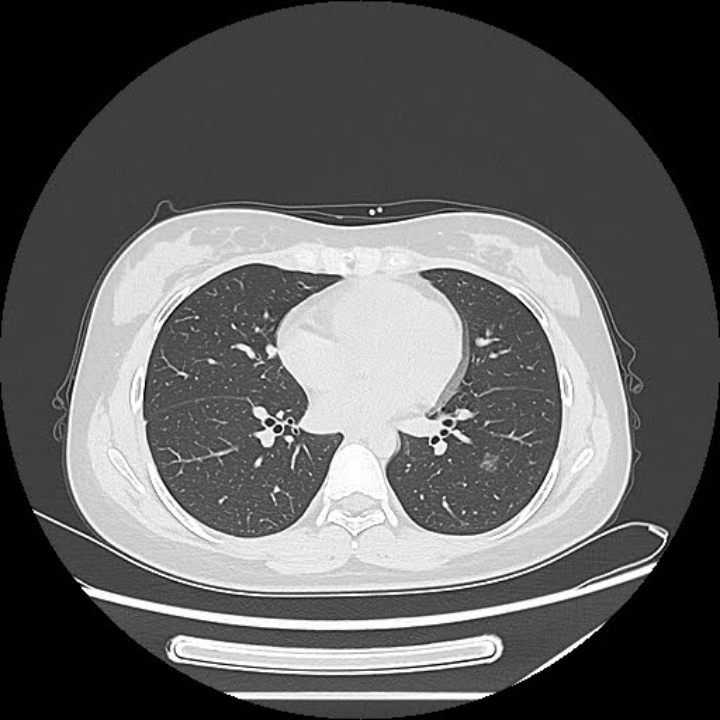

图片55.png

图三:纯磨玻璃结节